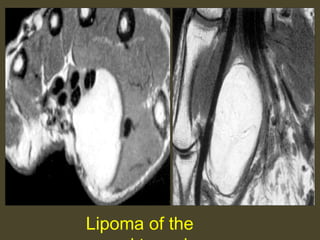

Lipoma of the

Carpal tunnel syndrome caused by cysticercosis.

Lipoma at the Ulnar tunnel.